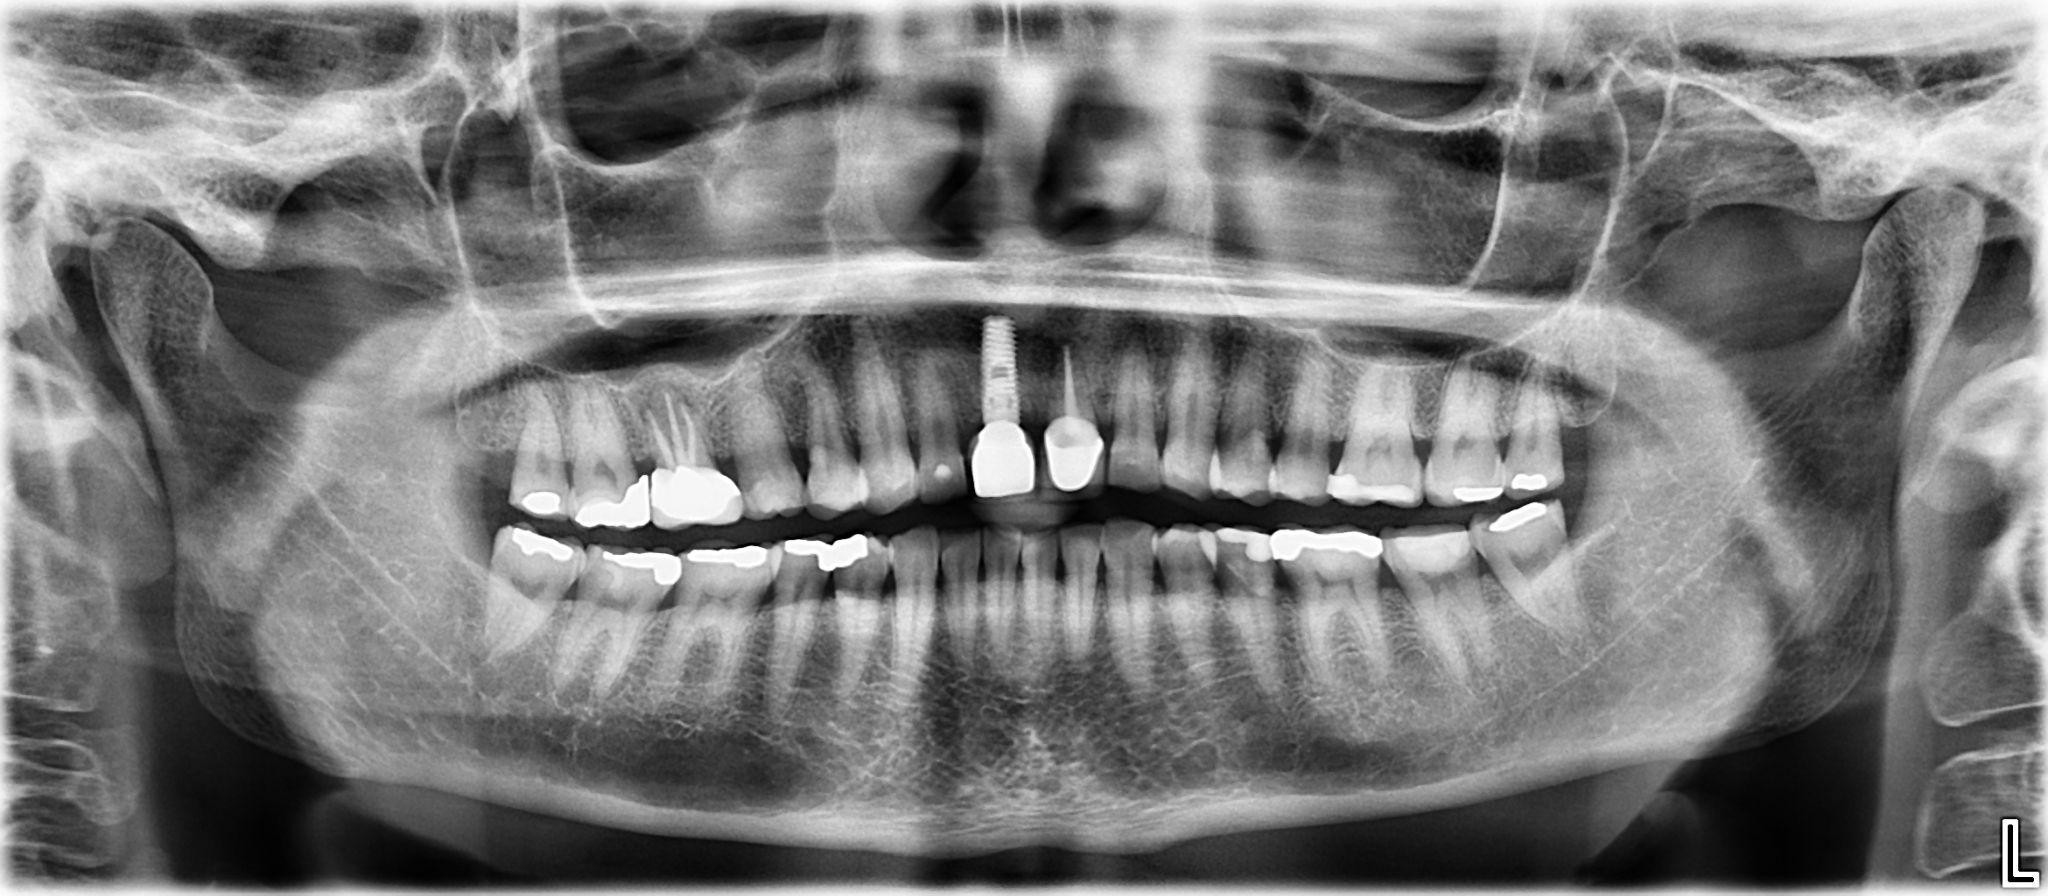

1. What option cannot be selected for the first quadrant of this panoramic X ray?

2 / 25

2. What option cannot be selected for the second quadrant of this panoramic X ray?

3 / 25

3. What option can be selected for the third quadrant of this panoramic X ray?

4 / 25

4. What option cannot be selected for the forth quadrant of this panoramic X ray?